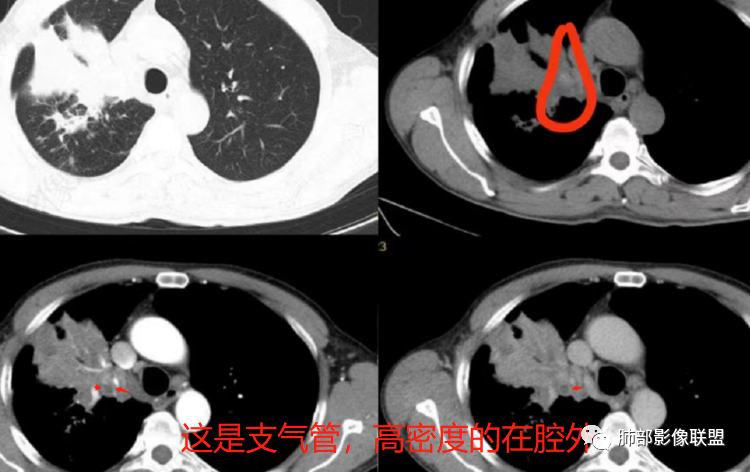

这是炎性的,支气管壁弥漫增厚,近端腔狭窄

这是肺癌的

这是腔内肺癌的

1、局部占位效应,支气管往往增大,而不是支气管狭窄

2、支气管壁破坏、不连续,腔外侵犯

3、占位效应大,局部肺动脉受压外移或侵犯